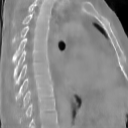

The results presented in Table 1 and 2 show our proposed method’s performance on unconditional 3D brain MR and chest CT image generation. Our proposed approach not only outperforms most comparing methods in FID and MS-SSIM metrics, it also has the lowest inference GPU memory footprint at a resolution of and was the only diffusion-based method that could be trained at a resolution of . Operating in the wavelet domain and profiting from the reduced spatial dimension also results in a relatively short inference time of / at the respective resolutions. Compared to the results presented in [23], we did not find that incorporating wavelet information into the network’s feature space (WavU-Net) increased the model’s performance. Qualitative results of our proposed method (WDM) are shown in Fig. 2 and 3. A qualitative comparison of samples produced by all evaluated methods can be found in the Supplementary Material.